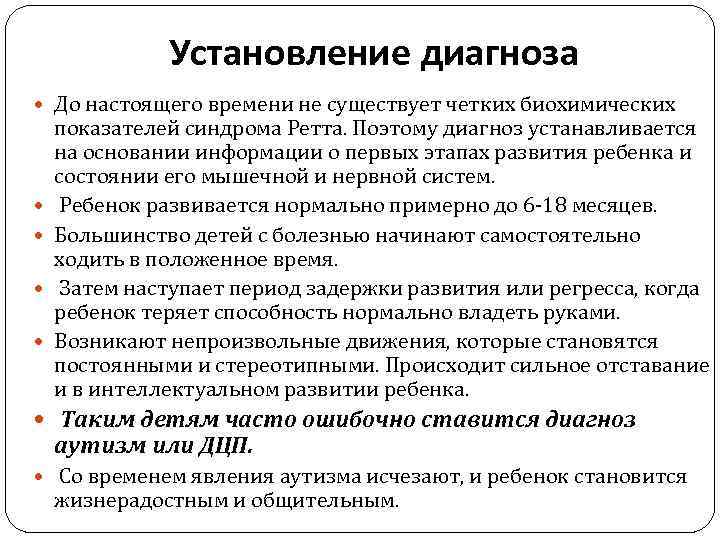

Установление диагноза До настоящего времени не существует четких биохимических показателей синдрома Ретта. Поэтому диагноз устанавливается на основании информации о первых этапах развития ребенка и состоянии его мышечной и нервной систем. Ребенок развивается нормально примерно до 6 -18 месяцев. Большинство детей с болезнью начинают самостоятельно ходить в положенное время. Затем наступает период задержки развития или регресса, когда ребенок теряет способность нормально владеть руками. Возникают непроизвольные движения, которые становятся постоянными и стереотипными. Происходит сильное отставание и в интеллектуальном развитии ребенка. Таким детям часто ошибочно ставится диагноз аутизм или ДЦП. Со временем явления аутизма исчезают, и ребенок становится жизнерадостным и общительным.